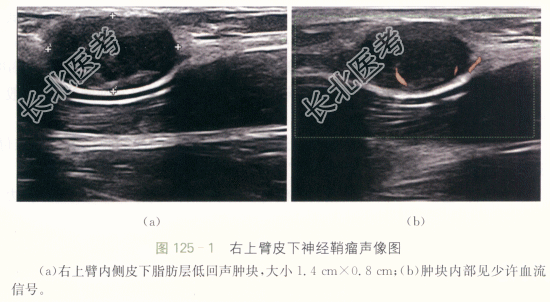

患者,男性,47岁,因“无痛性右上臂内侧肿块3年余”就诊。患者三年前发现右上臂内侧肿块,无明显疼痛,近期因肿块逐渐增大就诊。患者否认外伤史,否认手术史,否认其他器官肿瘤史。

患者右上臂内侧触及肿块,约1cm×1cm,质韧,边界清晰,可活动,无明显压痛,位于肱二头肌与肱三头肌之间,周围皮肤颜色正常,无皮肤破溃,无手术瘢痕。环小指偶有麻木,夹纸试验阴性。

皮下神经鞘瘤。